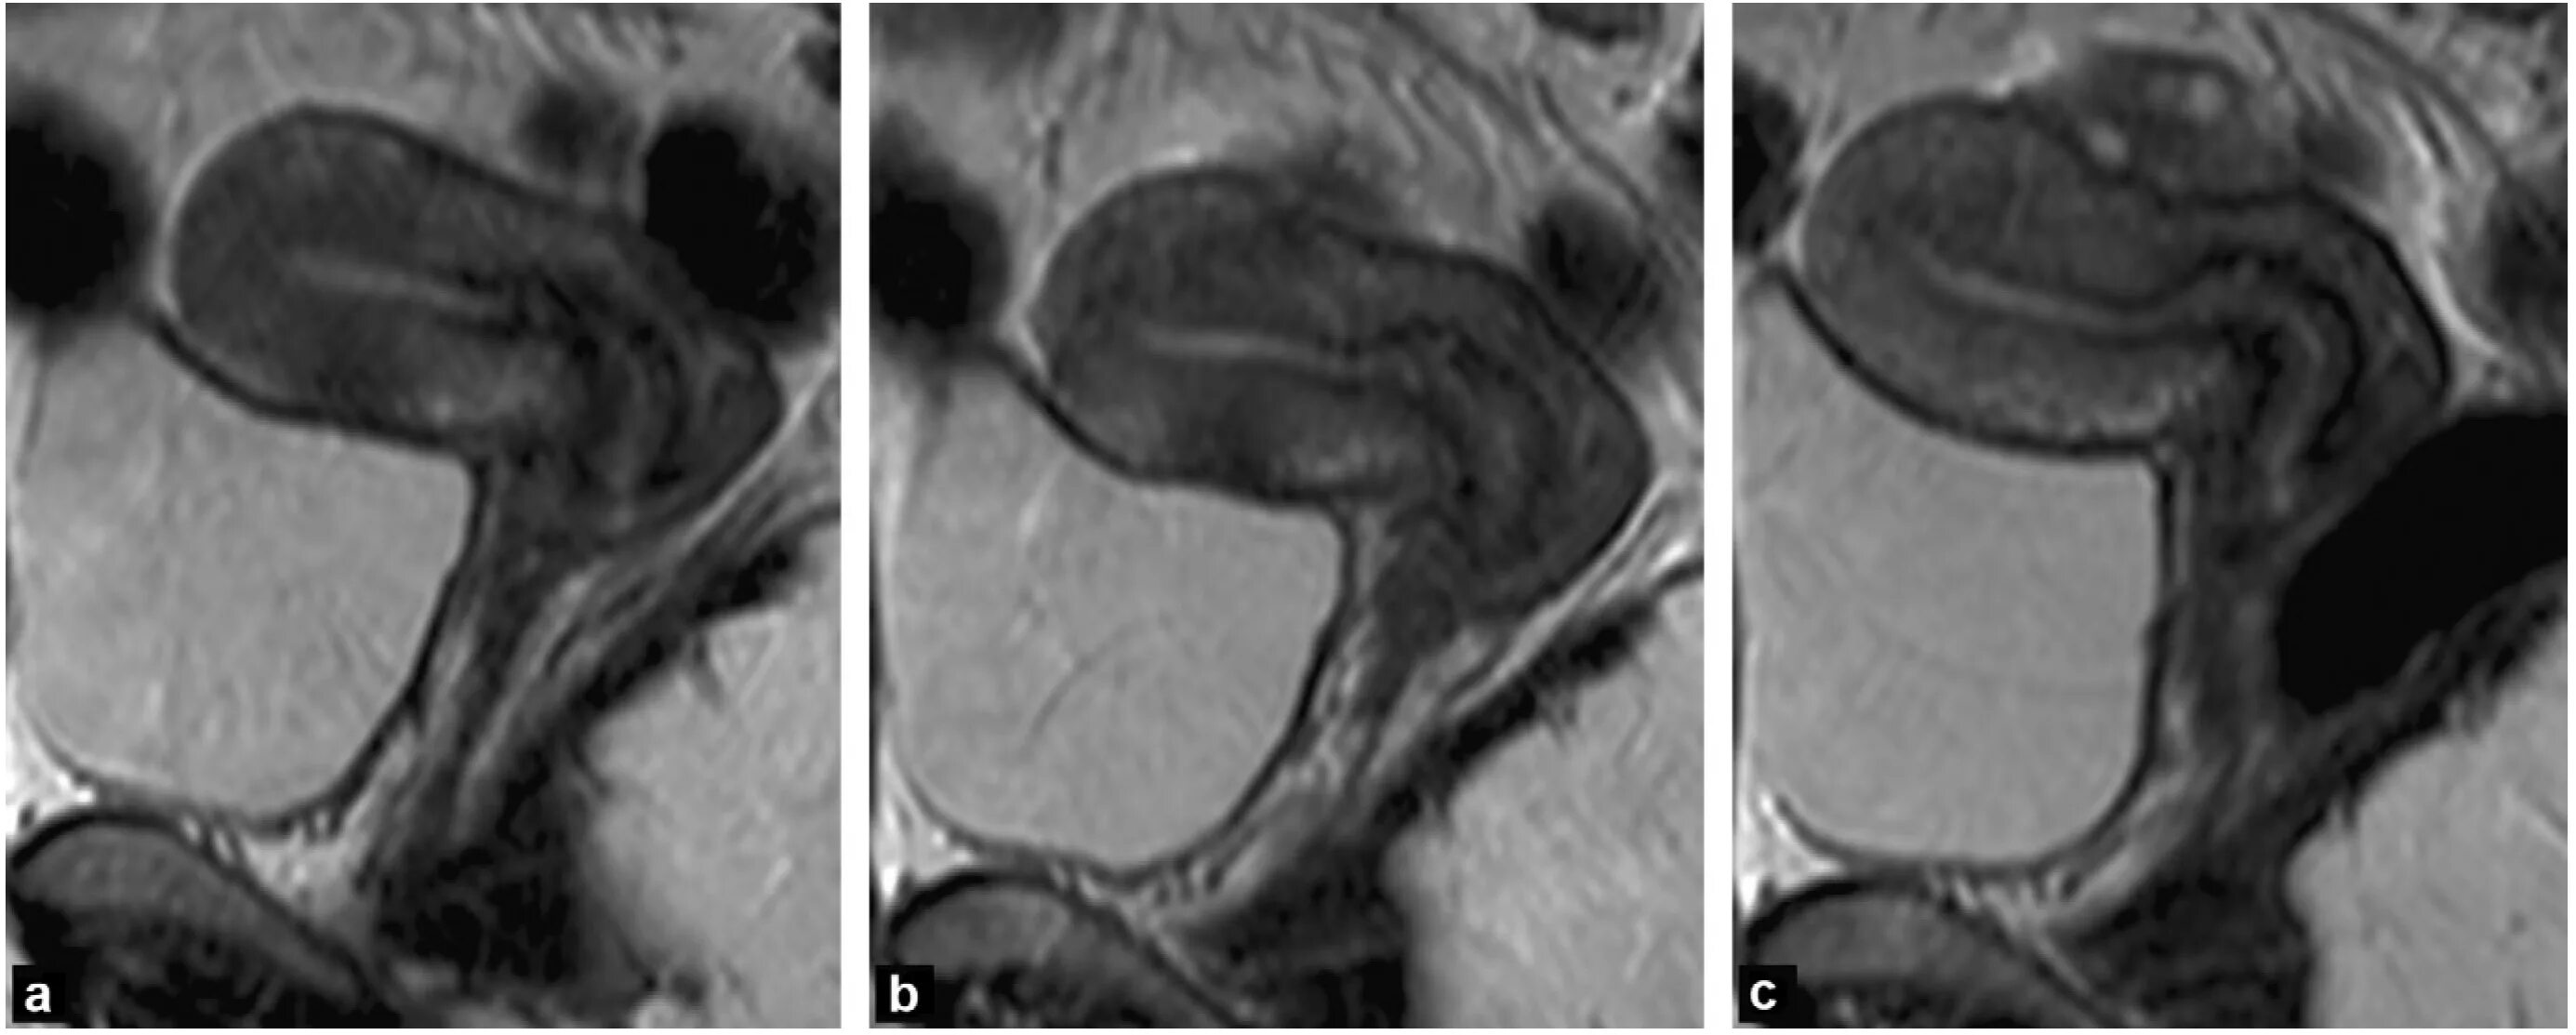

Диффузные изменения миометрия аденомиоз